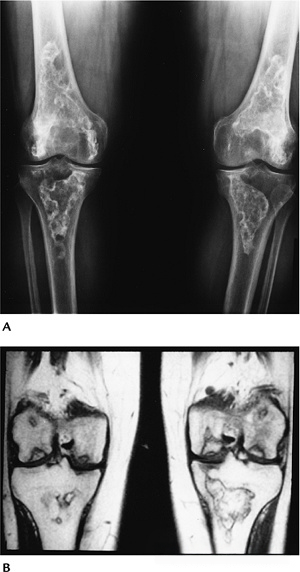

ffbc877f785f656b01216fb6a85c3f13.png

图-5髋关节缺血性坏死。T1像显示缺血性坏死,左侧更为严重。

816fffc5d8097e533c37f9acac40b5e5.png

图-6骨梗死。双膝站立位X光片显示双膝典型骨梗死的蛇行状边缘钙化。T1WI显示了梗死区和软骨下缺血性坏死。